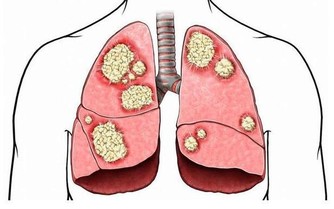

此外隱睾由於生長環境改變以及發育上在障礙,容易發生惡變。

當發現睾丸異常時要及時來醫院進一步檢查,隱睾是可以隱藏在腹腔、腹股溝管內環等處。

目前超聲檢查是最簡便,快捷無創的檢查方法,它不僅可檢查隱睾所在的位置,還可測量隱睾大小。